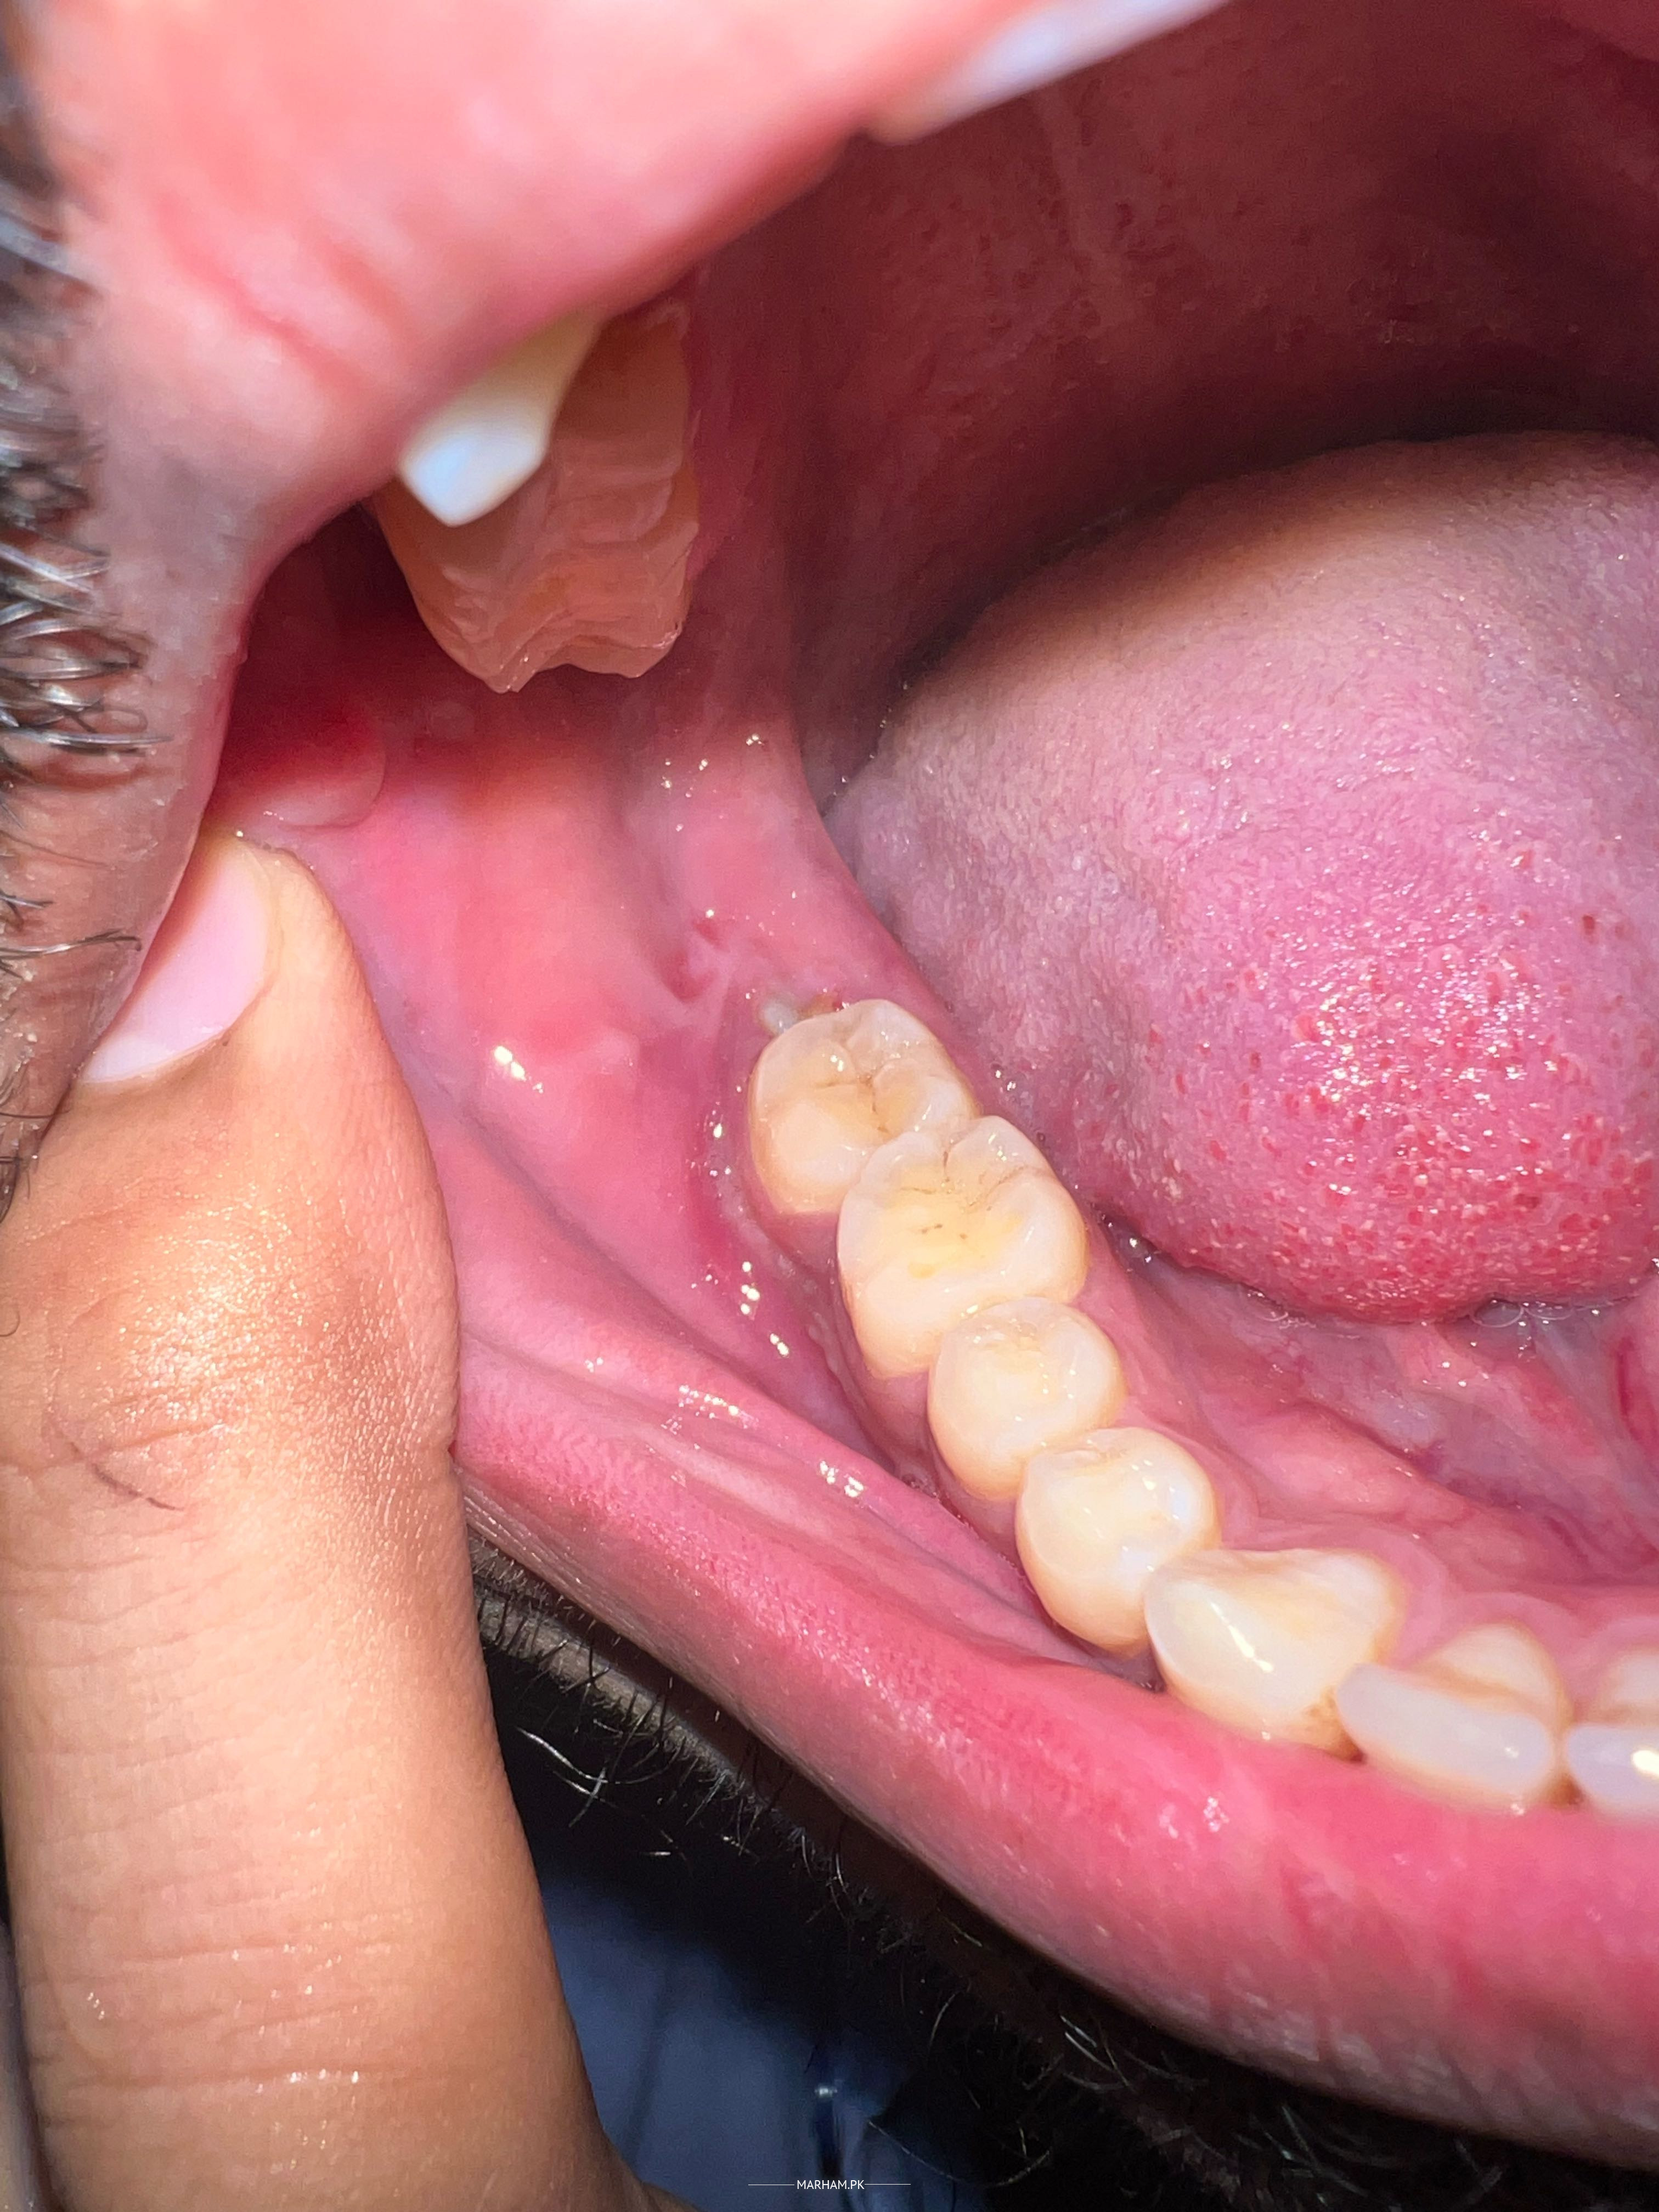

Asking For Self, Male, 22 Years old, lahore

Hello dr mujhe right side pr wisdom tooth hai us ka sath boht drd ho rha asy jesy gum ka andr pani bhr gaya ho boht drd hai pic mai dekh salty hain ap mai mark kia hai plz guide me

you have impacted third molar(wisdom teeth) that requires immediate surgical extraction

Hello, your wisdom tooth needs to be taken out. Either the space is less or its not at proper position so it won’t come out as ur other teeth. This procedure is very common and is internationally recommended in this situation.